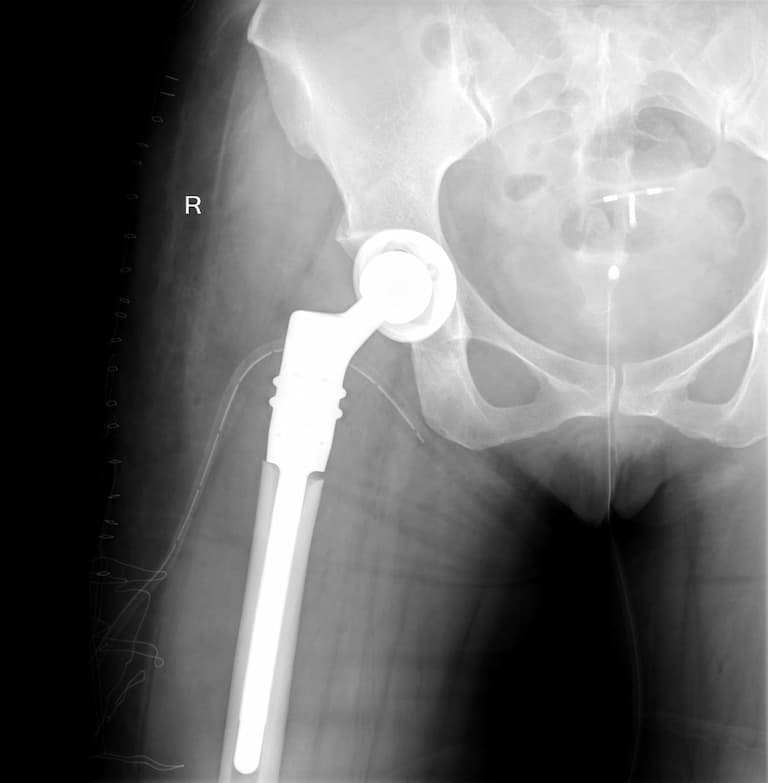

Түнхний үе солих мэс засал гэж юу вэ image3

Мэс заслын өмнөх болон дараах рентген зураг